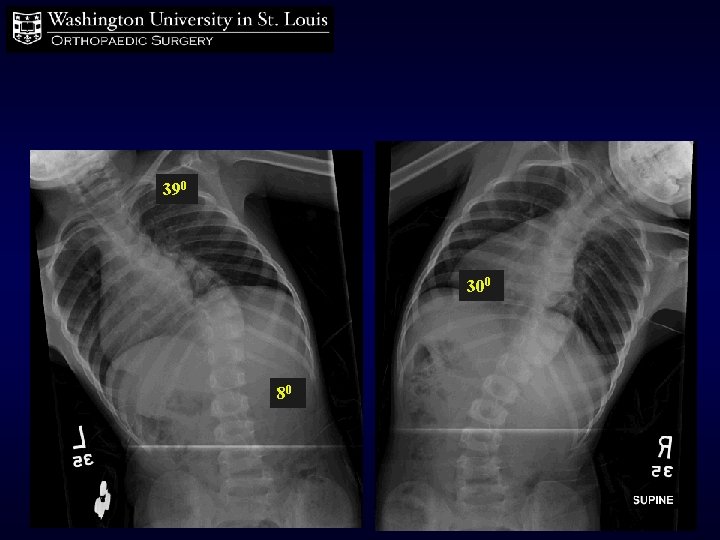

390 300 80

5+0 years 6 Spine casts 390 670 370 550 390 Standing 330 310 Supine